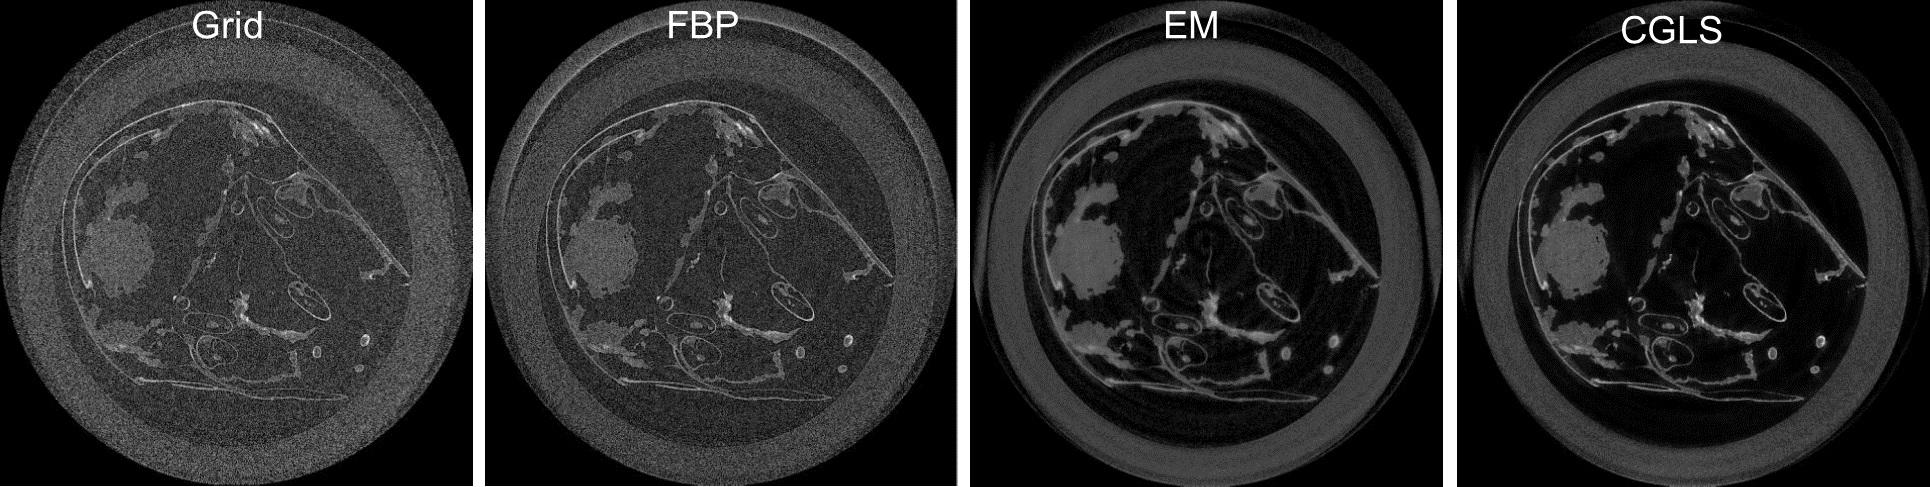

-提供FBP、Grid、EM等多种重建算法,利用Grid网格算法能够在数秒内完成对图像尺寸为2k*2k的投影数据集的三维重建计算

图2 不同重建算法得到的重建结果